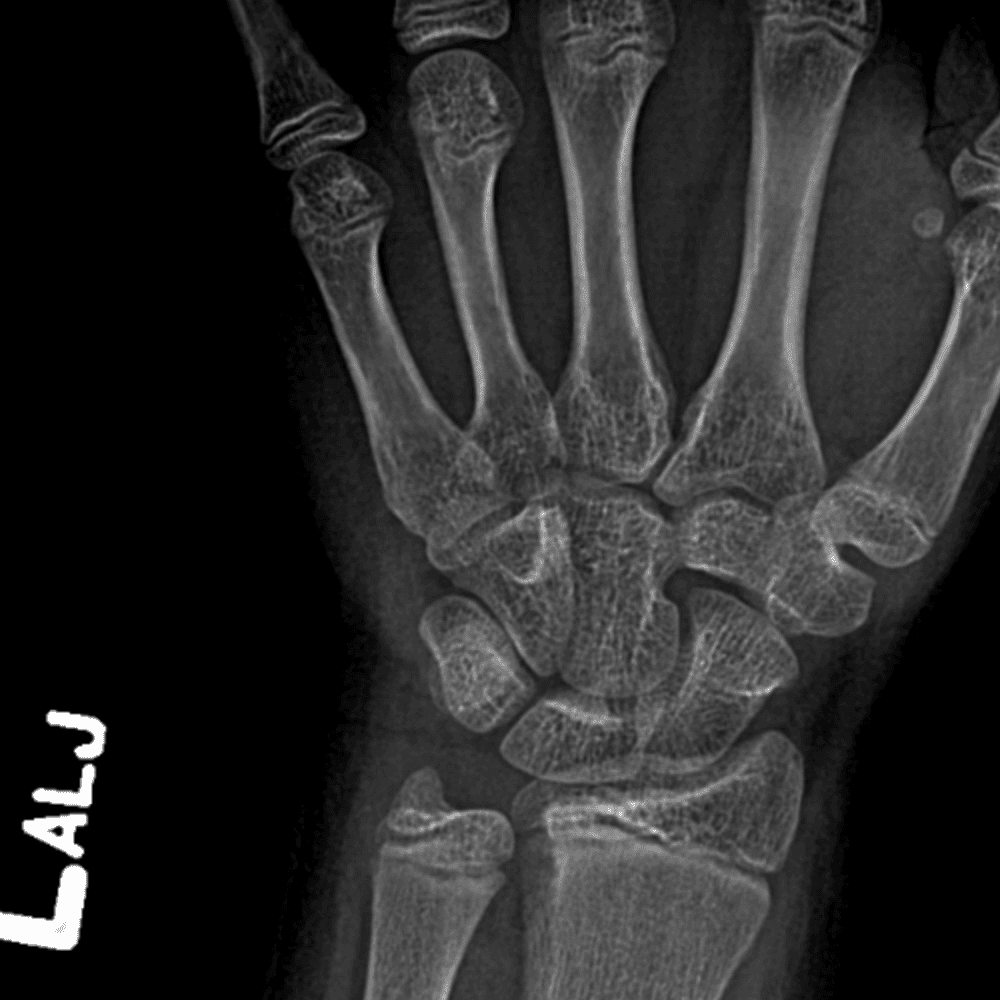

Simulates call by including subtle or difficult cases and some normals.

30 cases